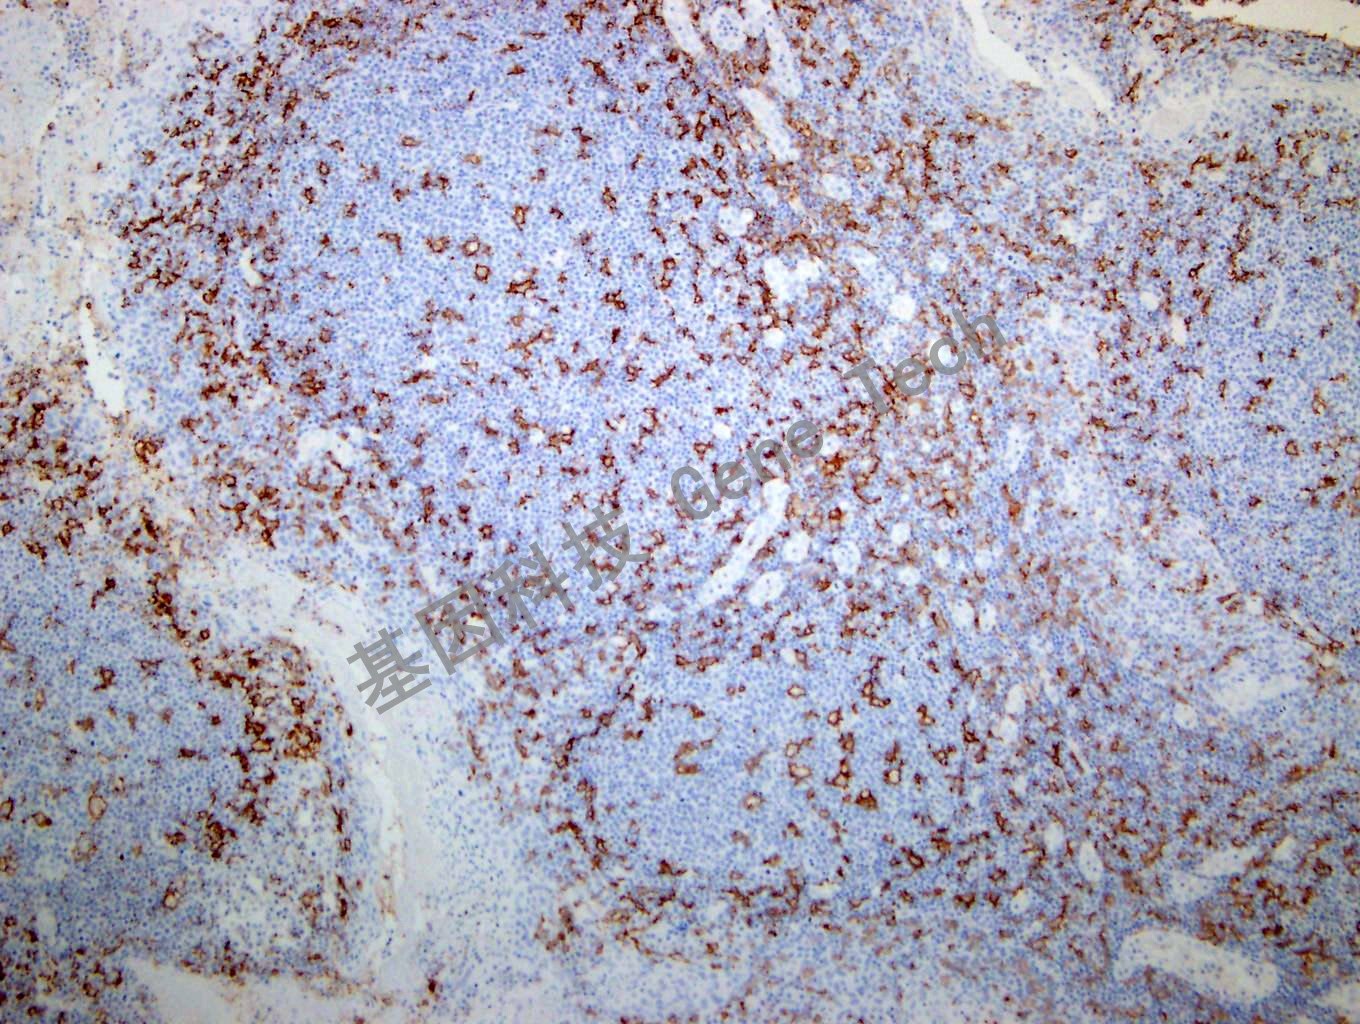

| 扁桃體石蠟切片,用 CD11c(GT2270)染色,細胞膜陽性,DAB 顯色。(10×) | ||

| 簡介:CD11c 是一種I 型跨膜蛋白,屬于整合素α 鏈蛋白家族,又稱IGTAX。可與整合素β2 形成異源二聚體,是白細胞特異的整合素組成形式。同時該二聚體還是非激活補體C3b 的受體4CR4),參與粒單核細胞與活化的內(nèi)皮細胞粘附過程,參與補體包被顆粒物被吞噬清除過程。CD11c 在人體大多數(shù)樹突狀細胞中有高表達,此外在單核細胞、中性粒細胞、巨噬細胞及部分B 細胞中也會有表達。在毛細胞白血病、急性非淋巴細胞白血病和某些B 細胞來源的慢性淋巴細胞把血病中有表達。CD11c 推薦作為抗體組合的一部分,有助于血液系統(tǒng)惡性腫瘤的診斷以及組織內(nèi)巨噬細胞 / 樹突狀細胞的鑒別。 | ||